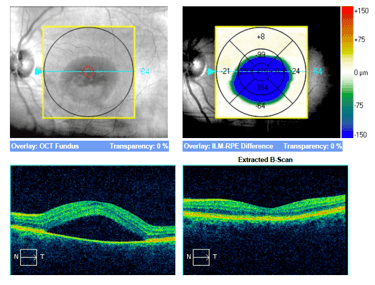

1. SOCT. Jest zwykle pierwszym badaniem wykonywanym u pacjenta z podejrzeniem CSCR. W postaciach prostych, ostrych najczęstszym objawem jest obecność hiporefleksyjnej przestrzeni płynowej pod siatkówką sensoryczną oraz wydłużenie fotoreceptorów. Dodatkowo obecne jest zwiększenie grubości siatkówki sensorycznej – obrzęk. Przy postaciach skomplikowanych mogą być obecne także ogniska PED. W miarę trwania CSCR wydłużenie fotoreceptorów zmniejsza się i zostaje zastąpione przez ziarnistości odpowiadające skupiskom makrofagów. W niektórych sytuacjach SRF może zawierać hiperrefleksyjne ogniska odpowiadające fibrynie (taki obraz jest charakterystyczny dla CSCR w trzecim trymestrze ciąży). Postaci długotrwałe CSCR zwykle wykazują bogactwo objawów widocznych w SOCT. Charakterystyczne jest ścieńczenie siatkówki sensorycznej, niekiedy cystowate zmiany w siatkówce sensorycznej, ubytki w RPE oraz ogniska PED.

Stan po klasycznej fotokoagulacji laserowej siatkówki. Pacjent po wielokrotnej laseroterapii mikropulsowej – bez resorpcji płynu podsiatkówkowego. Wykonano ponownie FA i wykonano ogniskową laseroterapie na podstawie wyniku badania (zaznaczony okrąg). W SOCT widoczna całkowita resorpcja plynu, ale również znaczne ścieńczenie siatkówki.